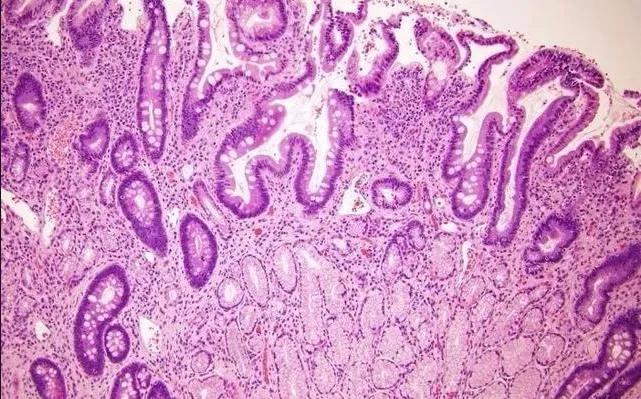

病理切片成品